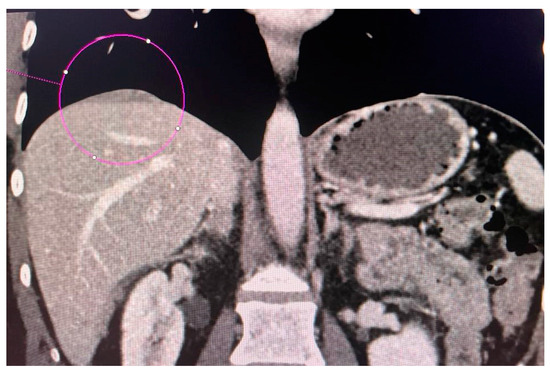

2.3. Computed Tomography Examination